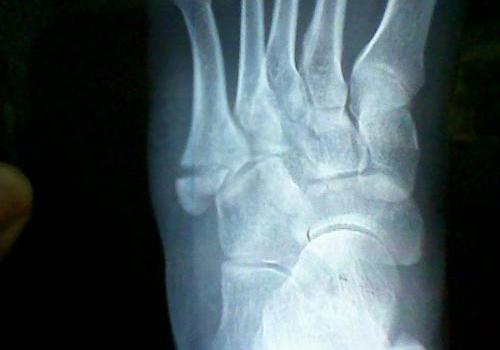

骨折后一般都会出现局部肿胀的现象,但是有些患者即使过去一个月了,肿胀的部位迟迟不能消退,这又是为什么呢?

骨折没复位

骨折一个月仍然肿胀有可能是因为骨折后没有完全复位导致局部组织仍然受到压迫而使得血液流通不畅,骨折部位肿胀。